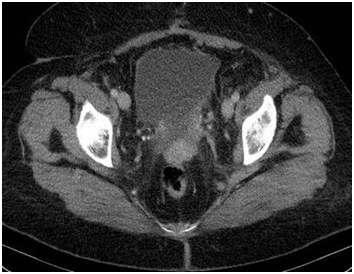

Peritoneal carcinomatosis was stated during the intraoperative review and verified histopathologically in all patients. Most often the peritoneum in pelvic and central abdominal region were harmed, both with equal percentage 90%. Small intestine peritoneum, except the proximal jejunum, was less affected with the lowest rate 50%. PCI was in the range from 5 to 28 (average index - 19) (Figure 2) (Figure 3). These are the areas of typical dissemination processes in peritoneum:

1. Recto-uterine pouch (the Douglas space);

8. Small-bowel mesentery (Figure 4‒7).